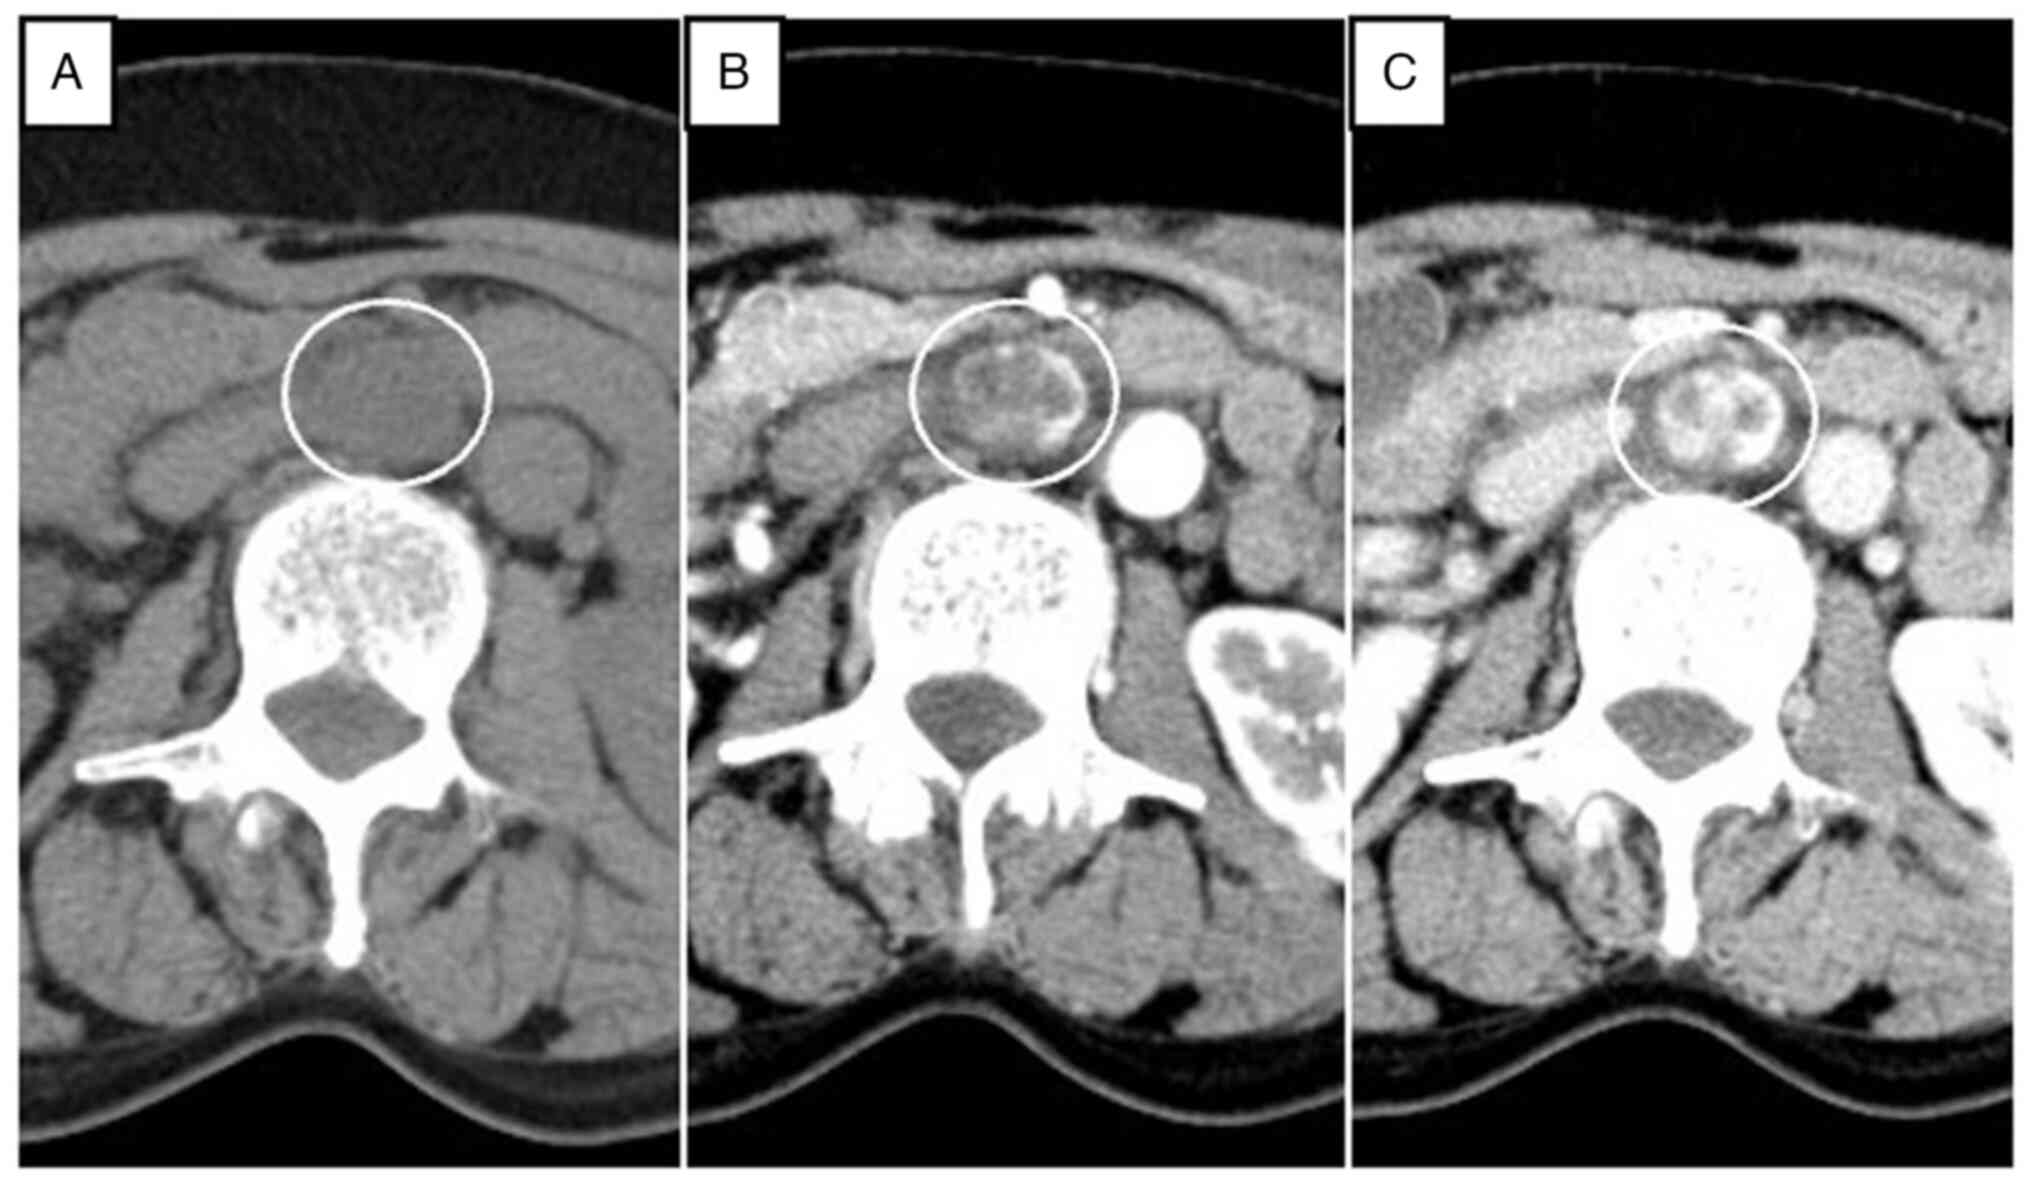

Anastomosing hemangioma (AH) is rare and a newly recognized variant of capillary hemangioma that is mostly found in the genitourinary tract. Additionally, AH is sometimes difficult to diagnose without pathological specimens. It is difficult to diagnose preoperatively due to the lack of specific clinical and radiologic appearance. The present report describes the imaging features from a radiological perspective and outlines the clinicopathologic features and treatment options. A 67‑year‑old woman was referred to Dokkyo Medical University Saitama Medical Center (Koshigaya, Japan) for a retroperitoneal tumor that was identified at a medical checkup 4 years prior. The patient had no symptoms, no abnormal physical signs and no past medical or specific family history. Routine blood tests were all within the normal ranges. A nonenhanced CT scan showed a circular, homogenous, well‑circumscribed retroperitoneal tumor that was ~32x23 mm in size, between the abdominal aorta and the inferior vena cava, and just below the left renal vein. On a contrast‑enhanced multidetector CT scan, the tumor showed heterogeneous septal enhancement in the arterial phase and persistent enhancement in the portal phase. The tumor was diagnosed as a benign neurogenic tumor or a retroperitoneal cavernous hemangioma at the time, and the patient was intended to be followed up at the outpatient clinic. However, it gradually increased to a maximum diameter of 35 mm over 4 years. Finally, it was completely resected by open laparotomy and pathologically diagnosed as AH. Retroperitoneal hemangioma is extremely rare in adulthood and has been confirmed in only 1‑3% of all retroperitoneal tumors. To the best of our knowledge, only 6 cases of para‑aortic AH have been reported. The incidence of this variant is very low. However, AH may be included in the differential diagnosis when a slowly progressing heterogeneous mass appears in the para‑aortic region that exhibits a CT‑enhanced pattern similar to a typical cavernous hemangioma.